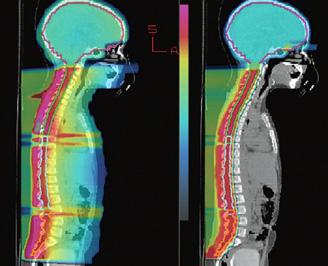

Figura 1. Leziune decelată colonoscopic la 25 cm de OA Figura 2: Îngroșare parietală asimetrică la nivelul joncțiunii recto-sigmoidiene Figura 3. Adenocarcinom moderat diferențiat, cu arhitectură tubulară